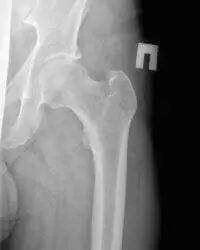

- Перелом шийки стегна – найчастіша травма. В основному, превалює у людей похилого віку. Пов’язано з остеопорозом і зниженням міцності кісткової тканини. Відзначається болем як при ходьбі, так і в спокої, набряком в місці травми, великої гематомою. На рентгені тазостегнового суглоба буде видно лінію перелому в області шийки стегна, а також зміщення відламків. Проводиться як в одній (прямий) проекції, так і в двох (прямий і аксіальної з відведенням хворого стегна, з метою виявлення більш точного розташування уламків).

Картина, видима при рентгені ТБС

Знімки робляться в двох проекціях: передньо-задній (прямий) і бічний. В першу чергу на рентгенограмі лікар-рентгенолог бачить анатомічна будова кісток таза і тазостегнового суглоба

- тазові кістки (крила таза; клубова кістка, седалищная кістка, лобковий симфіз – вони утворюють вертлюжної западини, яка є місцем прикріплення головки стегнової кістки до тазу)

- крижі

- ручку

- голівка стегнової кістки

- шийка стегнової кістки

- тіло стегнової кістки

У процесі розшифровки рентгена тазостегнових суглобів, лікар оцінює стан кісток таза; головки, шийки і тіла стегнової кістки.